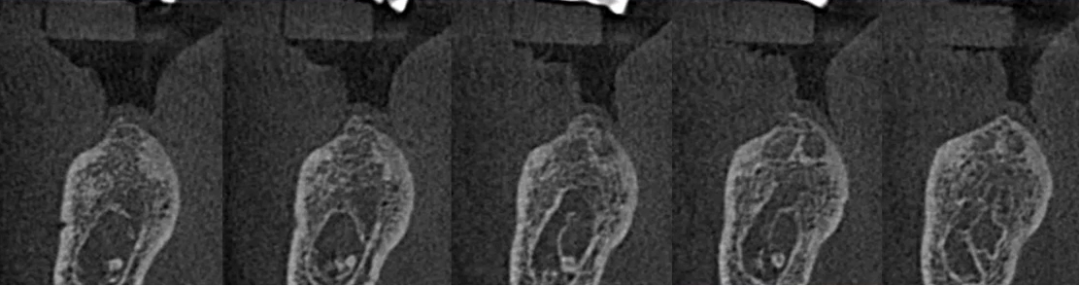

局部小视野CBCT检查

曲面断层片怎么看口腔精读 | 一次性教你看懂曲面断层片!_https://www.jmylbn.com_新闻资讯_第65张

神经管位于46、47位置膨大,上壁不清。